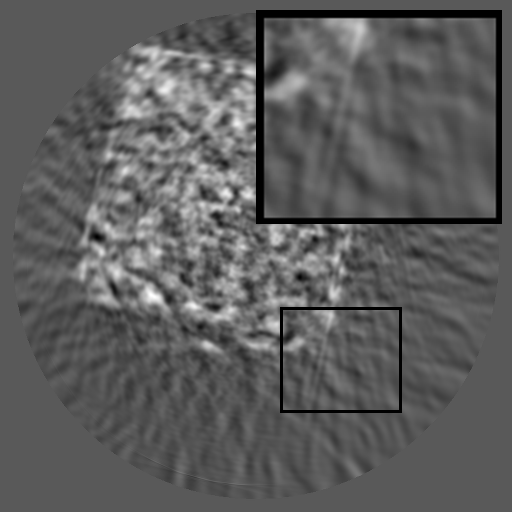

Refer to caption

(a) RGB Img

(b) RGB Spec

(c) Sino Img

(d) Sino Spec

Figure 1: Comparisons of RGB and sinogram and their spectra. Unlike RGB images, which have localized frequency components, sinograms exhibit structured spectral distributions due to the Radon transform.

Unfortunately, most existing inpainting methods are developed for RGB images [liu2024structure, zhang2023coherent, ko2023continuously, deng2022hourglass, lugmayr2022repaint, li2022misf, suvorov2022resolution], where missing regions can be locally inferred from surrounding pixels. However, such spatial assumptions fail in X-ray sinograms, where each pixel represents an integrated projection value along an X-ray path, causing globally entangled structures. Several studies have explored sinogram completion using U-Net- [zhao2018unsupervised, yao2024no], GAN- [valat2023sinogram, xie2022limited] or Transformer-based [jiaze2025sinotx] models, and some have incorporated periodicity or reconstruction-based constraints [li2019sinogram, wagner2023geometric]. However, these methods remain largely spatial, focusing on pixel-wise interpolation or appearance realism, and fail to explicitly model the structured frequency domain or the governing physics of sinogram formation, which are fundamentally distinct from those of RGB images. As defined by the Radon transform [radon_uber_1917], the detector and angle axes of a sinogram represent distinct physical dimensions, leading to highly directional and asymmetric spectral patterns (see Figure 1). Recognizing these unique characteristics, we design a framework FCDM that explicitly leverages both the frequency-domain organization and physical consistency of sinograms for faithful and coherent restoration.